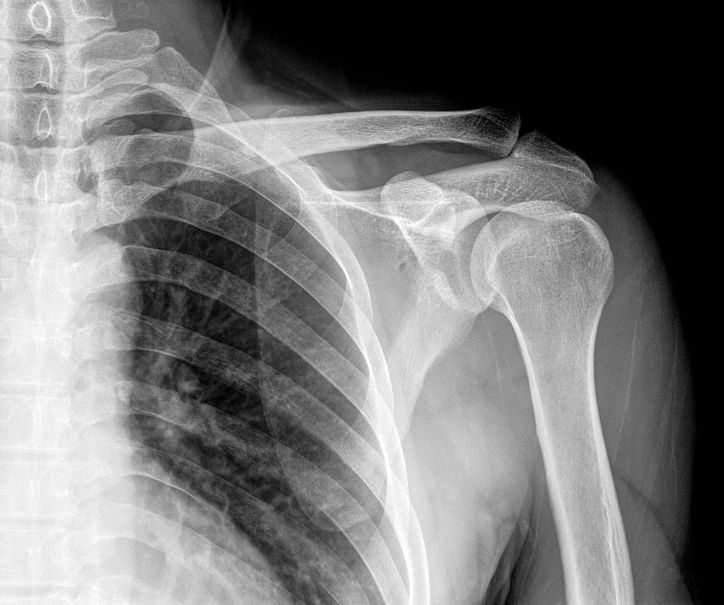

其实网上说的这些事儿,有 可能 是真实存在的,包括谢医生在门诊给肩痛的患者看病的时候,也会常规开一个 肩关节正位的X光片子 ,一方面是要看看肩关节的骨骼状态,是否有严重的增生,关节间隙的狭窄等;另外一方面是肩关节的正位片子往往会带着一侧的胸部,也会排除掉肺部是否有 巨大占位 压迫导致疼痛的可能,当然在做检查之前,谢医生不会跟患者说这第二方面的考虑,避免引起患者的 恐慌和焦虑 。